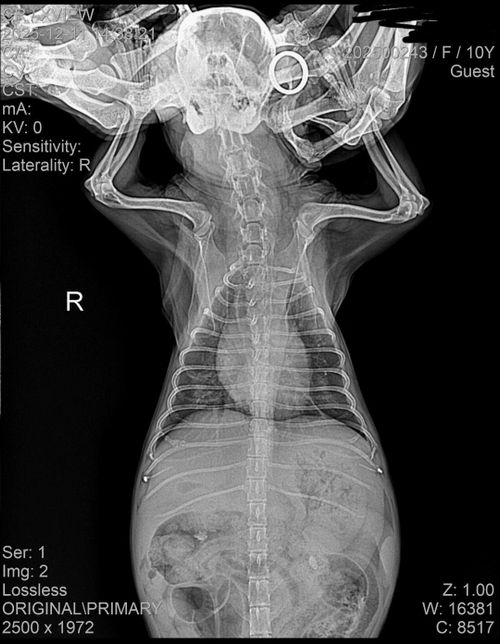

- 반려동물 건강반려동물탈퇴한 사용자강아지 폐수종 상태 확인 부탁드립니다.전에 목에 이물질이 걸려 이를 제거하는 과정에서 비심인성으로 폐에 물이 약간 차 이뇨제를 투약하고 입원을 시켰습니다.하지만 입원 다음 날, 폐에 물은 빠지지 않고 신장 수치만 하루 새 30이 증가했습니다. 이에 이뇨제 투약을 중단하고 경과를 지켜보기로 했습니다.그 다음 날, 신장 수치는 약 10 정도 낮아졌고 폐에 찬 물도 조금 빠졌다고 했습니다. 그래서 그 다음 날 퇴원을 계획했으나, 당일 아침 다시 확인해 보니 폐에 물이 더 찼다고 했습니다.병원 환경이 불편한지 배변을 잘 하지 못하고 있습니다. 다만 현재 신장 수치는 32이고, 호흡수도 나쁘지 않으며 식욕도 있는 편입니다. 병원에서 스트레스를 더 받게 두기보다는 집에 데려와 지켜보고 싶은데 괜찮을지 궁금합니다.아래 사진은 입원당시 사진입니다.1명의 전문가가 답변했어요